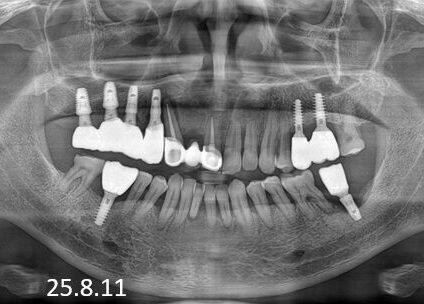

전악 임플란트